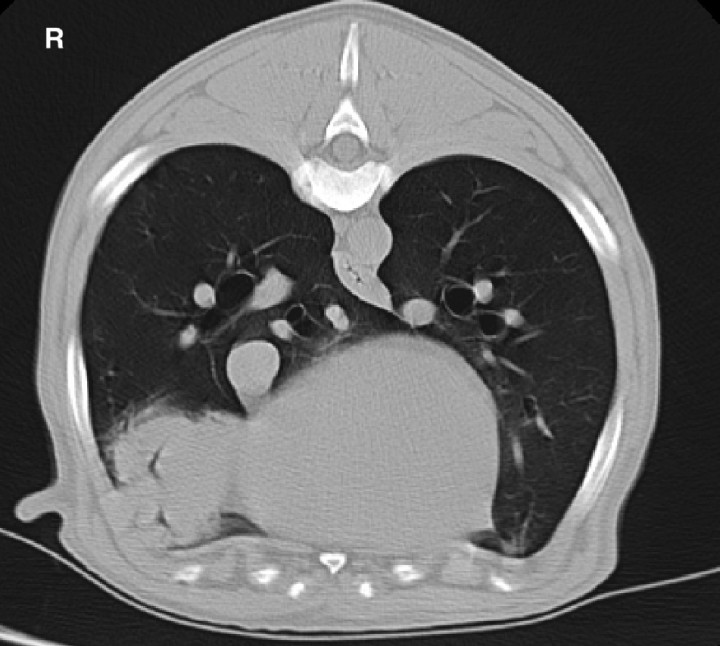

Pulmonary masses can be assessed by CT in order to better delineate margins and tumour extension for surgical planning along with imaging for concurrent pulmonary nodules and regional lymph nodes involvement. Carcinomas are the most frequently primary lung tumours in dogs and cats. Carcinomas are most commonly localized in the caudal lung lobes and described as solitary, well circumscribed, bronchocentric masses with internal air bronchograms, which can cause various degree of bronchial compression (Fig. 4). Other imaging features include contrast enhancement and internal mineralization. Cats in contrast to dogs tend to have more irregular margins and can show intratumoral cavitations and pleural effusion.[ Aarsvold S, Reetz JA, Reichle JK et al.: Computed tomographic findings in 57 cats with primary pulmonary neoplasia. Vet Radiol Ultrasound 2015; 56:272-277. [PubMed] , Marolf AJ, Gibbons DS, Podell BK et al.: Computed tomographic appearance of primary lung tumors in dogs. Vet Radiol Ultrasound 2011; 52:168-172. [PubMed] ] Canine pulmonary histiocytic sarcoma has been reported to present predilection for right middle or left cranial lung lobes (Fig. 5). Carcinomas generally metastasize to tracheobronchial lymph nodes but dogs with histiocytic sarcoma also show involvement of craniomediastinal and sternal lymph nodes.[ Tsai S, Sutherland-Smith J, Burgess K et al.: Imaging characteristics of intrathoracic histiocytic sarcoma in dogs. Vet Radiol Ultrasound 2012; 53:21-27. [PubMed] ]

<p>10 year-old Bernese Mountain dog with a well demarcated bronchocentric soft tissue attenuating mass in the right middle lung lobe. CT features are consistent with histiocytic sarcoma. R: right.</p>

10 year-old Bernese Mountain dog with a well demarcated bronchocentric soft tissue attenuating mass in the right middle lung lobe. CT features are consistent with histiocytic sarcoma. R: right.